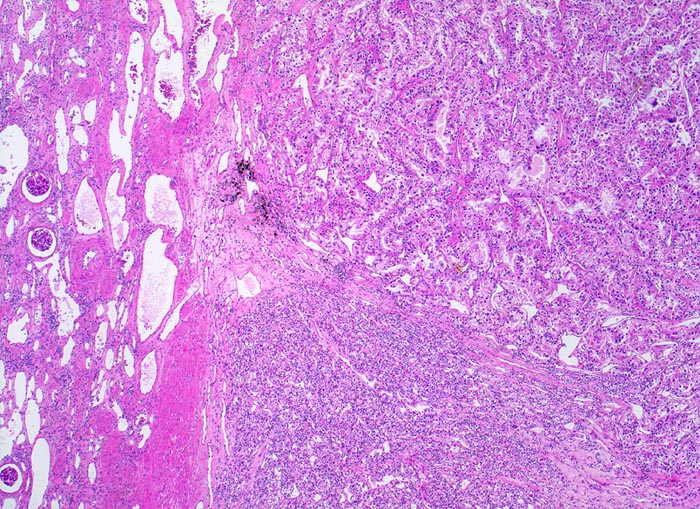

hellzelliges Nierenzellkarzinom

Die Grenze zwischen Karzinom und Nierenparenchym ist scharf und enthält zahlreiche erweiterte Gefässe. Das Karzinom bildet im oberen Anteil drüsige Strukturen, der untere Anteil erscheint solide.

Hellzellige Nierenzellkarzinome zeigen ein expansiv verdrängendes Wachstum an der Tumorinvasionsfront.